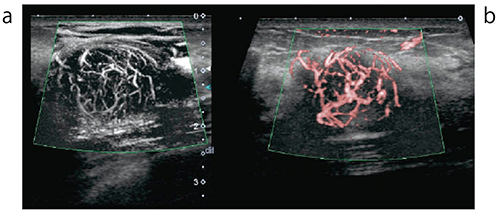

従来のモードに比較して低い流速をより分解能高く描出することを主眼に開発されてきたSMI。その表示方法は2種類あります(図2)。

・cSMI:カラー表示であるcolor-coded SMI。血流である可能性の高い信号のみを表示しています。カラーで表示することで一瞬の拍動性の血流に関して視認性が向上しています。

・mSMI:モノクロの表示であるmonochrome SMI。バックグラウンドのBモード画像を組織抑制のように消して,血流信号だけをモノクロで表示。血行動態を把握し,病変の識別の一助につながる可能性があります。

図2 線維腺腫(20mm×17mm×14mm)

a:mSMIの方がより低流速信号を記録できます。

b:cSMIは処理が加わるため,組織抑制のように血流情報を強調して表示できます。